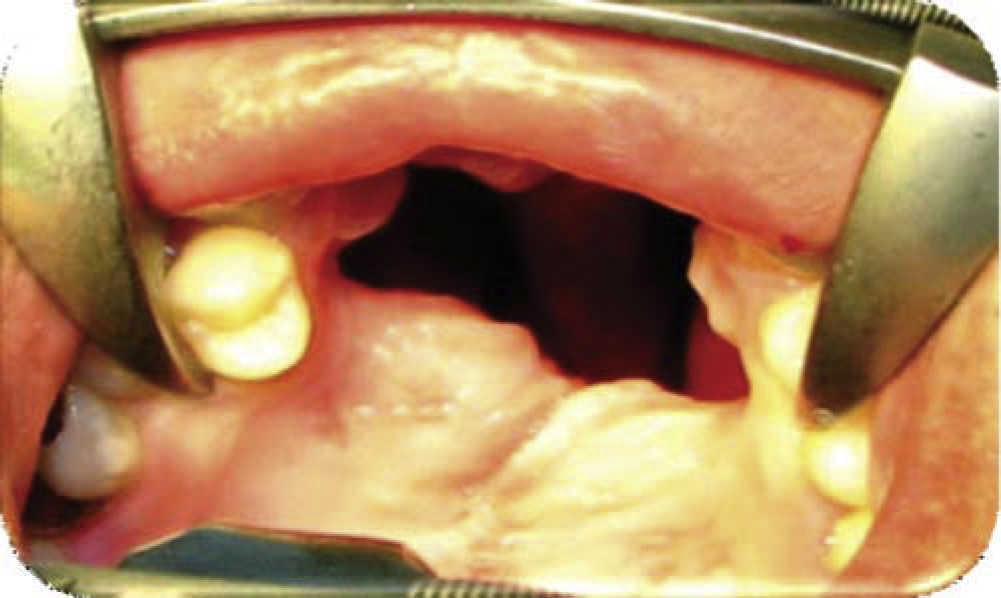

Physical exploration. 23 year old male patient. Intra-oral examination revealed cleft palate sequels, oro-nasal fistula measuring 2.5 × 2.5 cm at the anterior palatal region with communication to the nasal cavity, with healthy surrounding tissue (Figure 1).